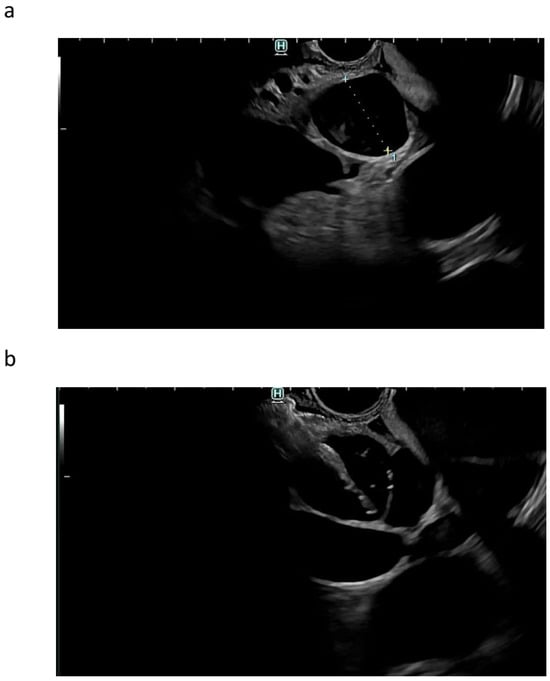

| Autor | Study Type | Patients | Adverse Events | Comments |

|---|---|---|---|---|

| Burmester et al. Gastrointest Endosc 2003 [3] | Single-center case reports | 4 | Bile leak (n = 1) | EUS-CDS, retrograde HJS, EUS-HGS. |

| Puspok et al. Am J Gastroenterol 2005 [87] | Case reports | 6 | Cholecystitis (n = 1) | EUS-guided transduodenal puncture of the common bile duct with stent placement. Transhepatic metal stent |

| Kahaleh et al. Gastrointest Endosc 2006 [88] | Retrospective study | 28 | Minor bleeding (n = 1), self-limited Pneumoperitoneum (n = 2) Bile leak (n = 1) | Rendezvous |

| Bories et al. Endoscopy 2007 [89] | Pilot study, single-center | 11 | Cholangitis (n = 1) | EUS-HGS |

| Yamao et al. Endoscopy 2008 [90] | Case reports | 5 | Pneumoperitoneum (n = 1) | EUS-CDS |

| Tarantino et al. Endoscopy 2008 [51] | Single-center | 9 | Death from liver cirrhosis complication 15 days after intervention (n = 1) | Transduodenal approach |

| Maranki et al. Endoscopy 2009 [52] | Single-center, retrospective | 49 | Pneumoperitoneum (n = 3), Bleeding (n = 1), Aspiration pneumonia (n = 1) | Transgastric-transhepatic (intrahepatic) or transenteric-transcholedochal (extrahepatic) |

| Horaguchi et al. Dig Endosc 2009 [91] | Single-center | 16 | Peritonitis (n = 1) | EUS-BD via duodenum, stomach, esophagus |

| Brauer et al. Gastrointest Endosc 2009 [92] | Comparative study, single-center nonrandomized observational study | 20 | Pneumoperitoneum (n = 1) Respiratory failure (n = 1) | Transenteric-transcholedochal extrahepatic approach for biliary cases |

| Park et al. Gastrointest Endosc 2011 [7] | Comparative study, prospective follow-up study. | 57 | Postoperative adverse effects after EUS-EUS-BD: 20%: bile peritonitis (n = 2), mild bleeding (n = 2), and self-limited pneumoperitoneum (n = 7) Late adverse effecta: distal stent migration—7%. | In multivariate analysis, needle-knife use was the single risk factor for post-procedure adverse events after EUS-BD |

| Hara et al. Am J Gastroenterol 2011 [93] | Prospective study | 18 | Peritonitis (n = 2) Bleeding (1) | EUS-CDS |

| Artifon et al. J Clin Gastroenterol 2012 [13] | Randomized controlled trial | 25 | Bile leak (n = 1) Mild bleeding (n = 1) | Percutaneous transhepatic biliary drainage and EUS-BD |

| Kim et al. World J Gastroenterol 2012 [94] | Two-center study | 13 | Peritonitis (n = 1) | EUS-CDS and EUS- HGS, fully nitinol-covered self-expandable metal stent |

| Gupta et al. J Clin Gastroenterol 2014 [10] | Multicenter, nonrandomized retrospective study. | 240 | Pneumoperitoneum 5%, bleeding 11%, bile leak/peritonitis 10% and cholangitis 5%. | Extra- and intrahepatic BD access. No significant difference between IH and EH approaches; benign and malignant indications |

| Will, et al. Ultraschall Med 2015 [8] | Single-center database over a 10-year period | 95 | Elevated cholestasis parameters (n = 3) | EUS-BD |

| Vanella et al. EIO 2020 [95] | Retrospective | 104 | Perforation (n = 2), Bleeding (n = 3), Bile leak (n = 1), Cholangitis (n = 9), Bacteriemia (n = 3), Acute Pancreatitis (n = 4), Severe abdominal pain (n = 2) | EUS-guided intrahepatic access, including rendezvous, antegrade stenting, and EUS-HGS |

| Füldner et al. Z Gastroenterol 2021 [86] | Prospective EUS-BD registry (2004–2020) | 103 | Complication rate: (n = 26/25%): stent dislocation (n = 11), perforation (n = 1), pain (n = 2), hemorrhage (n = 6), biliary ascites/leakage (n = 3) and bilioma/liver abscess (n = 3); major complication rate (n = 12/68—17.6%). | Different approaches of EUS-BD |

| Venkatachalapathy et al. Gastrointest Endosc 2021 [96] | Prospective multicenter study | 20 | Cholangitis (n = 1/5%), Stent migration (n = 1/5%) | EUS-CDS, lumen-apposing metal stents |

| Marx et al. Endosc Ultrasound 2022 [97] | RCT | 35 | Bleeding (n = 3/8.6%) Cholangitis (n = 1/2.9%) Peritonitis (n = 1/2.9%) Sepsis (n = 7/20%) | EUS-HGS |

| Ragab et al. Acta Gastroenterol Belg 2023 [98] | Prospective multicenter study | 91 | AE rate 18.7% for EUS-HGS, AE rate 8.9% for EUS-CDS. AE not specified. | EUS-HGS (n = 35) EUS-CDS (n = 48) |

| Bun Theo et al. Gastroenterology 2023 [28] | RCT | 83 | Cholangitis (n = 5) Stent misdeployment (n = 2) Stent migration (n = 1) Multi-organ failure (n = 2) Fatal (n = 4) | EUS-CDS with Hot Axios |